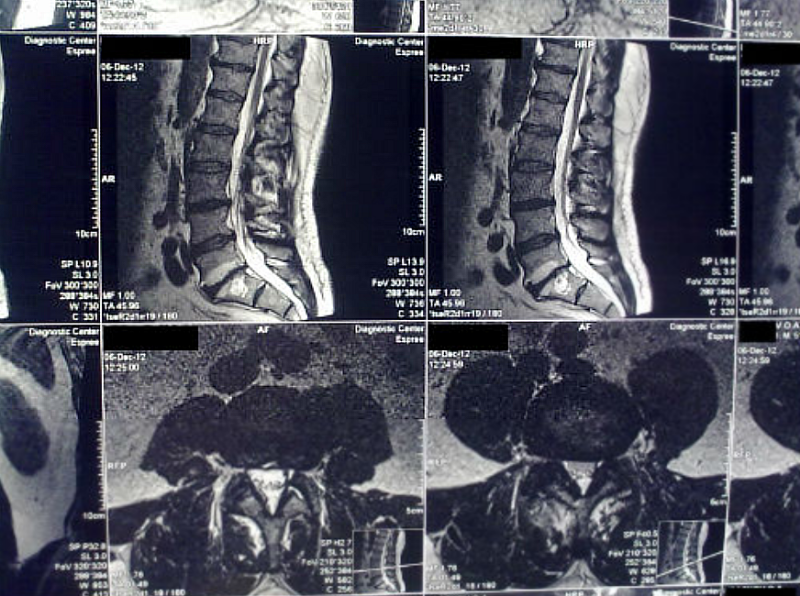

- Магнитно-резонансная томография (МРТ) спинного мозга: Это ключевой метод диагностики. МРТ позволяет визуализировать изменения в ткани спинного мозга, характерные для ишемии или кровоизлияния, а также исключить другие причины неврологических расстройств, такие как опухоли, травмы или воспалительные процессы. МРТ с контрастным усилением может быть использована для более детальной оценки состояния сосудов.

- Магнитно-резонансная ангиография (МРА) или КТ-ангиография: Эти методы позволяют визуализировать кровеносные сосуды, снабжающие спинной мозг, и выявить их сужения, закупорки или аномалии развития.